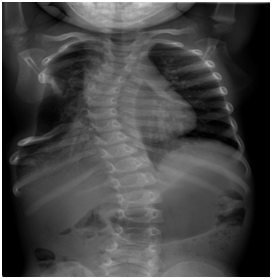

The neonate presented no signs of respiratory distress nor systemic failure. Plain radiograms shows the calcificated mass concerning to the 5th,6th, 7th ribs and the sternum with deterioration of the chest cavity Figures 2a&2b. Ultrasound of the area revealed a heterogeneous lesion, which casted significant acoustic shadow and was located symmetrically to the arches of the 6th, 7thand 8th left ribs. Multislice, low-dose CT scan was subsequently performed to clarify the origin, the extension and the configuration of the mass; 3D reconstructions were particularly helpful as they provided volumetric Figures suitable for preoperative planning Figures 3a&3b.

Figure 2a Plain radiogram of thorax. Is noted the large calcificated mass concerning to the 5th,6th, 7th ribs and the sternum.

Figure 2b Lateral plain film showing the protruding mass and the deterioration of thoracic cavity.